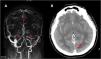

ResultsA total of 35 patients were included, with a median age at diagnosis of 50.3 (+/- 17.8) years, and the majority being women (74.4%). Nearly 95% of the patients presented at least one risk factor for the development of CVT. Heparins were used for the acute phase in 97.1% of cases, with 75% of those being low molecular weight heparins.During the first two weeks, a compound event (death, intensive care unit admission, National Institute of Health Stroke Scale at discharge >3, CVT recurrence, major bleeding, or the presence of complications) occurred in 28.6% of patients (10 patients).Over the mean follow-up period of 3.3 years, 14.3% of the patients died (with only one death attributed to CVT), one patient experienced major bleeding, and no patients had a recurrence of CVT.

ConclusionsIn our cohort, CVT predominantly affected young women with at least one risk factor for its development. The presence of edema on CT and corticosteroid treatment were associated with a poor short-term prognosis. However, we observed a favorable long-term prognosis in terms of mortality, recurrence, and bleeding.